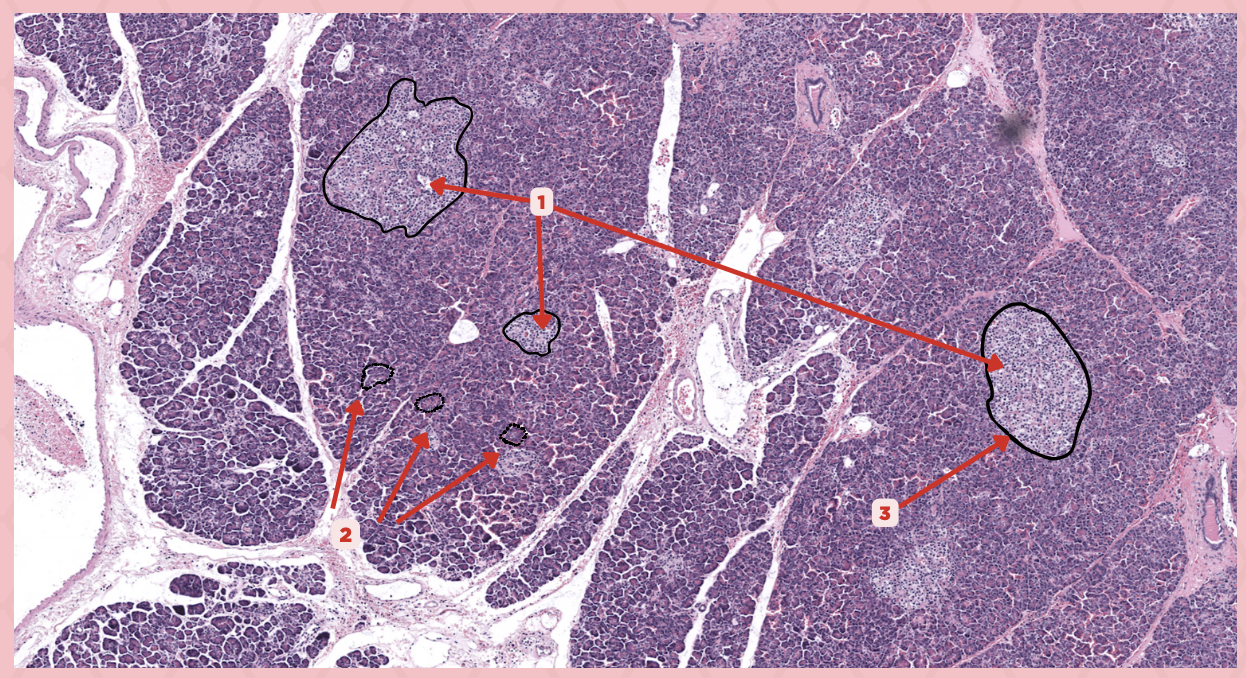

Pancreas

Identify the specimen.

Islets of Langerhans

Identify the structure labeled as 1.

Pancreatic Acini

Identify the structure labeled as 2.

Reticular Tissue

Identify the structure labeled as 3.

Beta-cells

Which cells occupy the central area of #1?

Pancreatic Acini

#3 delineates the pale- staining cells from the darker-staining cells. What do you call the darker-staining cells?